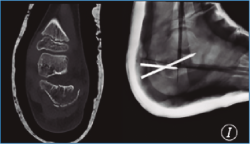

En nuestra serie, solo se aplicó reducción cerrada y fijación percutánea con agujas de Kirschner (AK) en un paciente de 7 años (Figura 2). La técnica quirúrgica tiene como objetivo introducir una AK a través de la apófisis y fisis para reducir la altura y longitud del calcáneo. Otra AK se introduce en el fragmento con la faceta posterior desplazada con el propósito de elevarla. Si fuera necesario, se puede introducir otra AK a través del córtex lateral para elevar los restos deprimidos de la articulación subtalar.

Figura 2. Fractura tipo Sanders III en un paciente de 7 años tras politraumatismo. Reducción y fijación mediante agujas de kirschner.